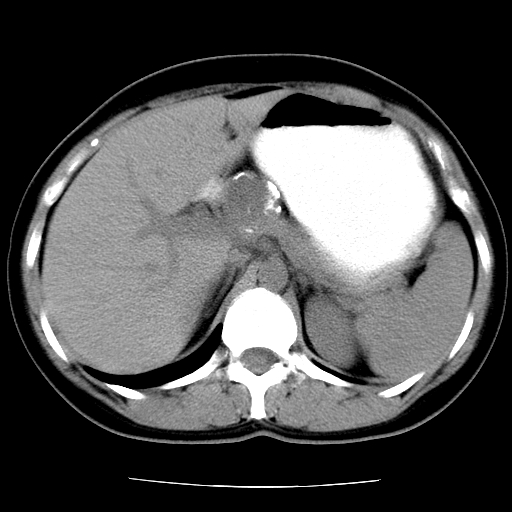

标题: CT16892:女40Y,急性阑尾住院!

女40y,急性阑尾住院!术前发现请会诊!

考虑门静脉瘤样扩张可能,建议增强扫描

胰头假性囊肿也有可能,建议增强

病灶位于门静脉的位置 ,有层面显示血管夹层样改变 ,考虑是门静脉瘤样病变1

病灶位于门静脉的位置 ,有层面显示血管夹层样改变 ,考虑是门静脉瘤样病变,建议进一步增强ct检查。

肝门区囊性占位,壁有钙化,考虑良性。来源难定。